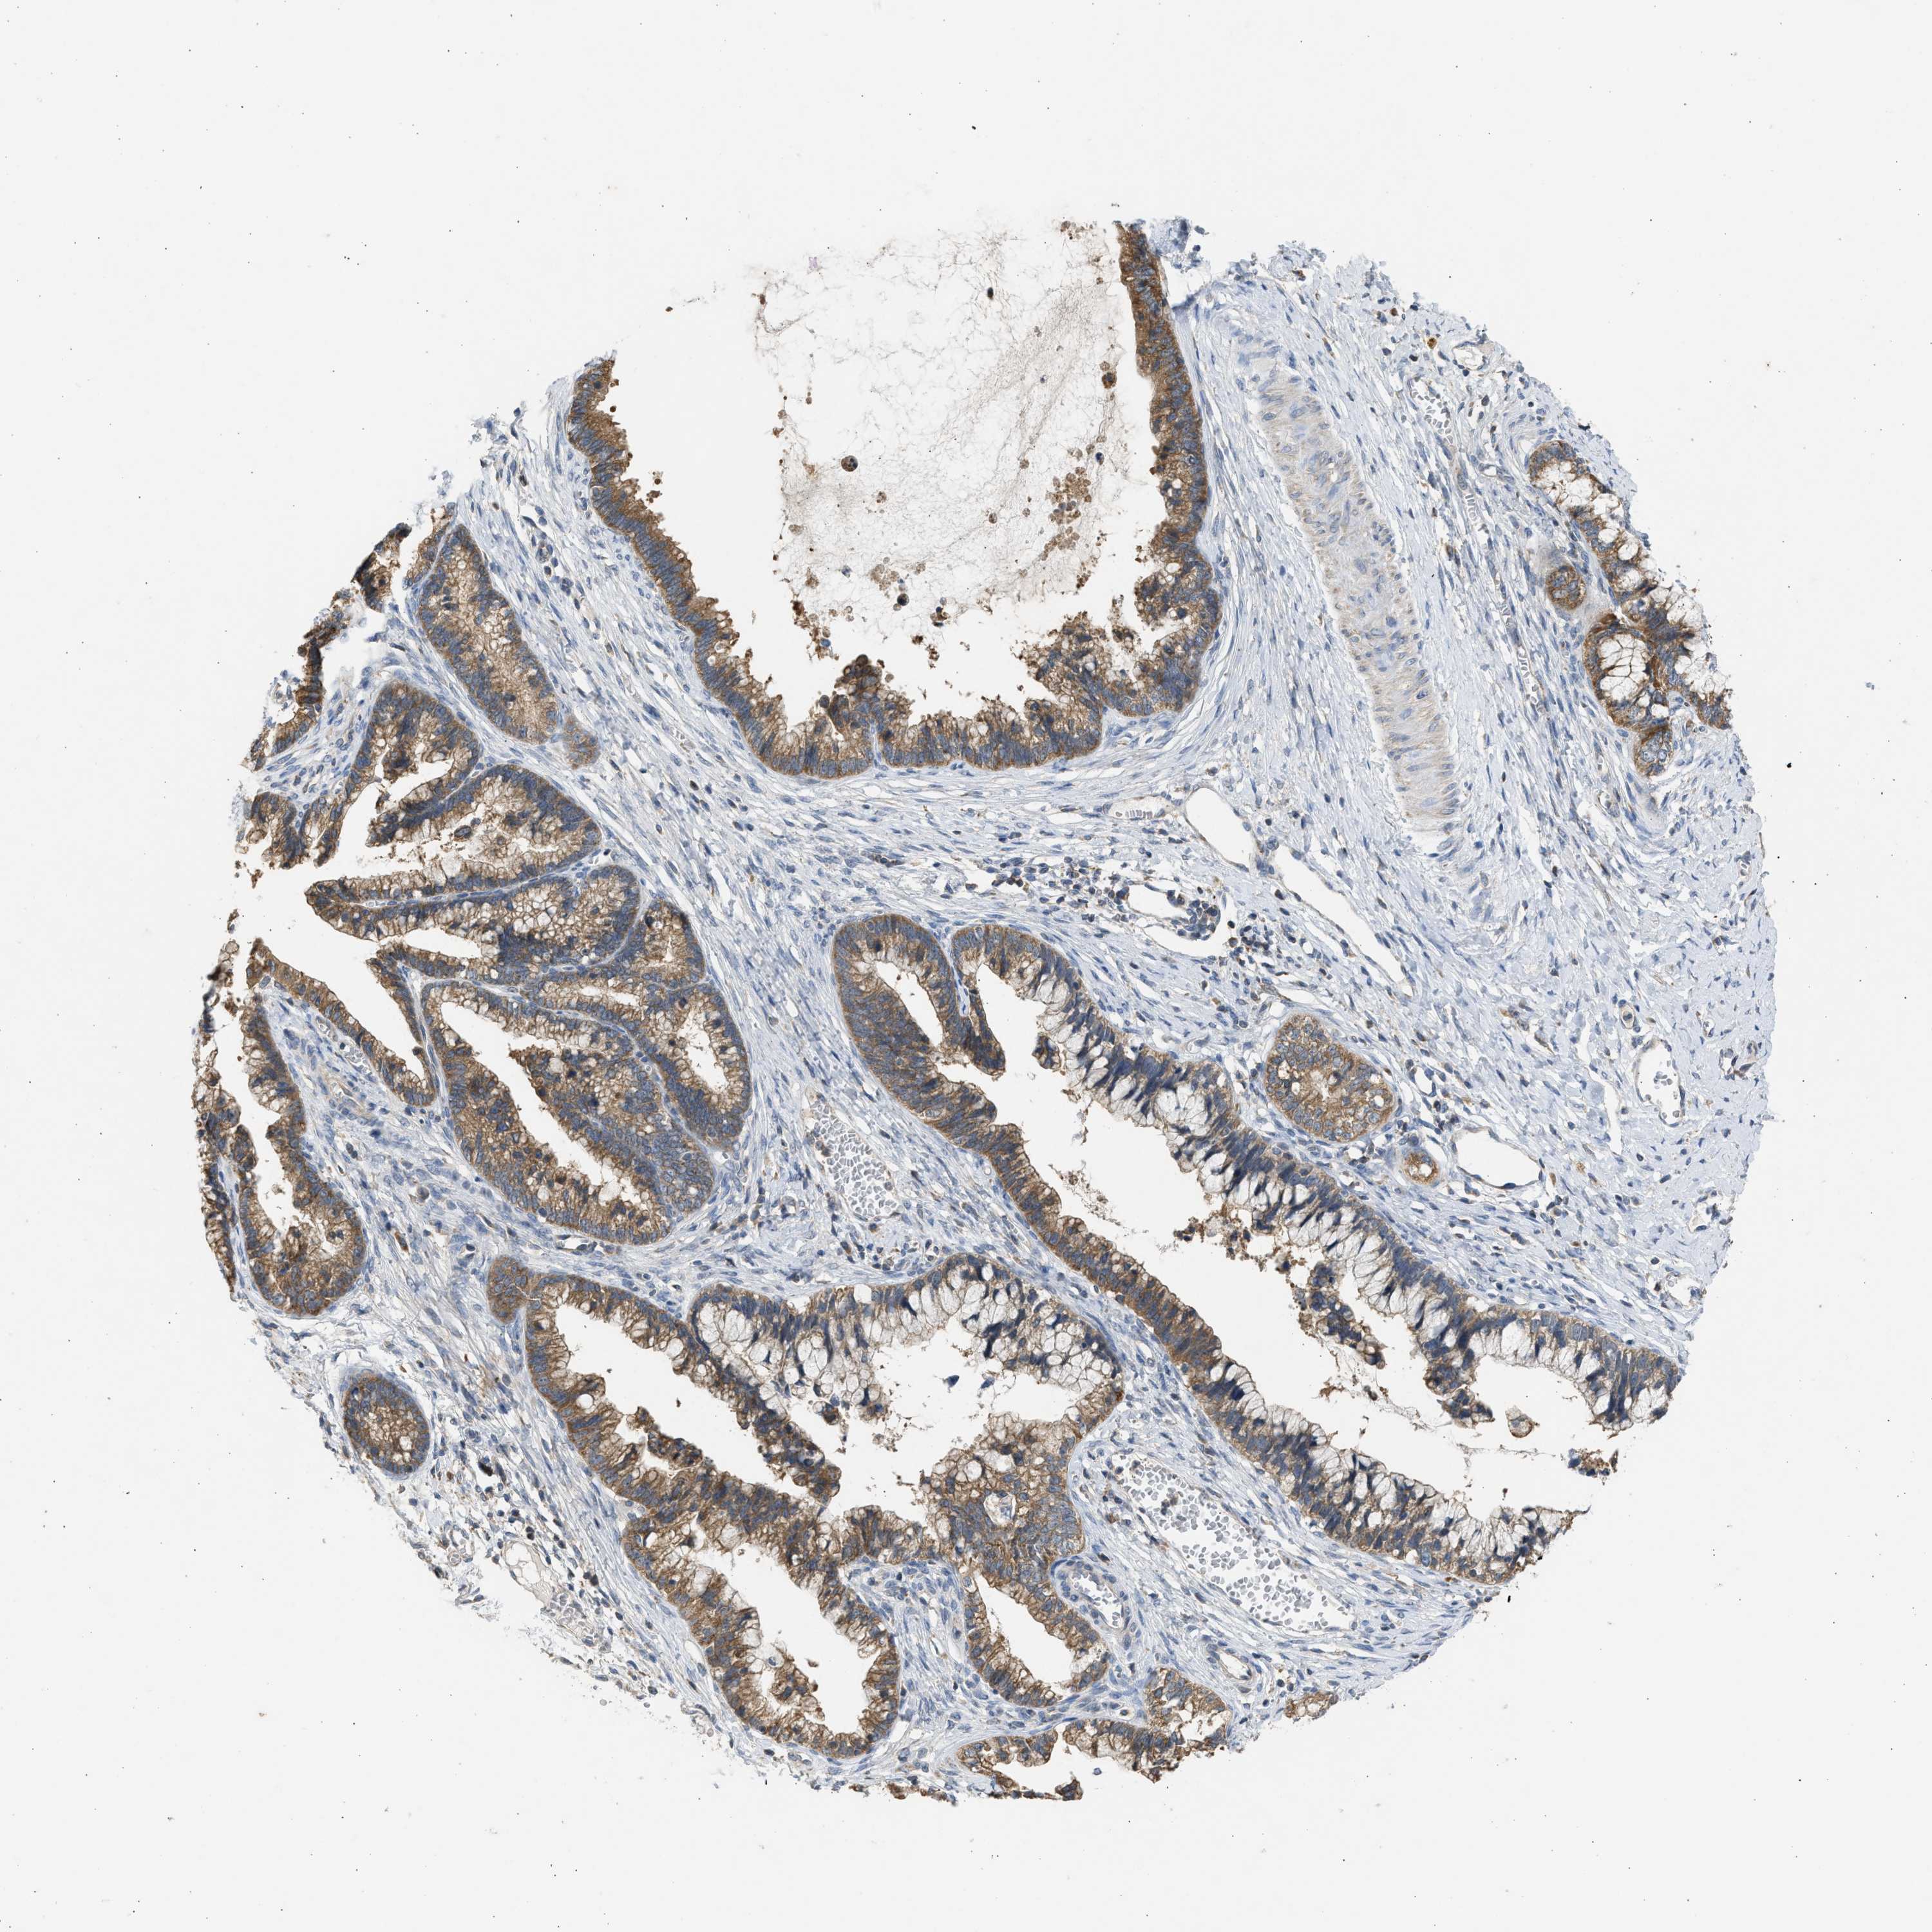

CERVICAL CANCER - Protein expressioni

A mouse-over function shows sample information and annotation data. Click on an image to view it in a full screen mode. Samples can be filtered based on level of antibody staining by selecting one or several of the following categories: high, medium, low and not detected. The assay and annotation is described here.

Note that samples used for immunohistochemistry by the Human Protein Atlas do not correspond to samples in the TCGA dataset.

Antibody stainingi

Antibody staining in the annotated cell types in the current human tissue is reported as not detected, low, medium, or high, based on conventional immunohistochemistry profiling in selected tissues. This score is based on the combination of the staining intensity and fraction of stained cells.

Each image is clickable and will lead to virtual microscopy that enables deeper exploration of all samples and also displays staining intensity scores, fraction scores and subcellular localization as well as patient and tissue information for each sample.

Antibody CAB018654

Squamous cell carcinoma, NOS

Adenocarcinoma, NOS